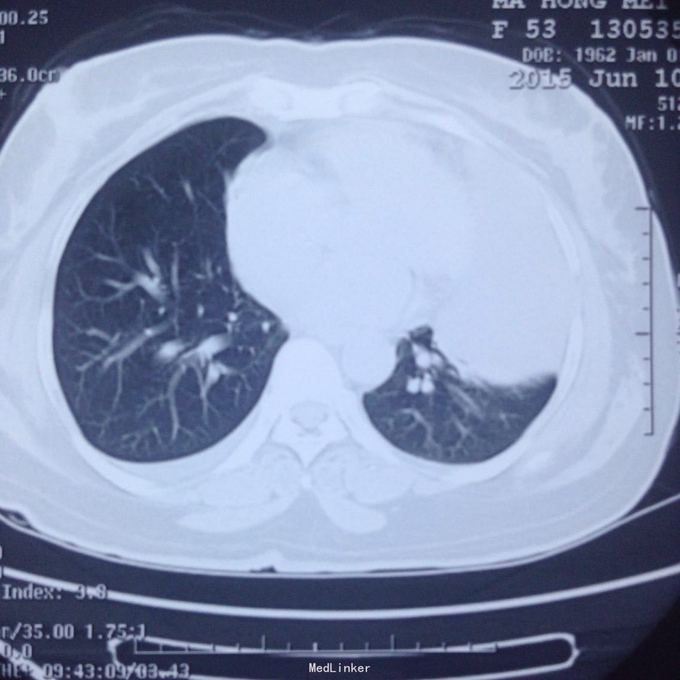

主诉:发现胸腔积液4月余。 现病史:患者4个月前因腰椎间盘突出在当地医院就诊,检查发现双侧少量胸腔积液,量不多,2个月后胸闷气短再次在当地医院复查胸部ct,提示双侧胸腔积液较前增多,左侧明显。

左侧胸腔包裹性积液? 完善胸腔b超提示左侧胸腔包裹性积液,最深处约59mm,内透声较差。予以定位后诊断性穿刺未抽出明显液体,当时考虑液体可能较粘稠或包裹分隔,遂决定予以小切口开胸探查。开胸后见胸腔积液,量约300ml,颜色较清亮,予以抽吸后在探查,见脏层及壁层胸膜无增厚及明显粘连,遂考虑不排除囊肿可能性,继续探查见胸膜顶靠近左纵隔处一囊壁,已破裂,囊壁挛缩成团,予以切除,术后病检为胸腺囊肿。

术后病检为胸腺囊肿。术后讨论:患者多次胸部ct均提示为包裹性积液,因囊肿较大,囊壁较薄,且靠近胸壁,易误诊为包裹性积液,但患者一直无发热病史,且复查ct积液位置靠胸前壁,术前应该考虑到囊肿可能,因患者经济较困难,至本院后未行增强ct,穿刺后考虑穿刺针将囊壁穿破,故开胸后未见完整囊肿,此类看似简单的病例容易由其他医院诊断误导,并且容易误诊。